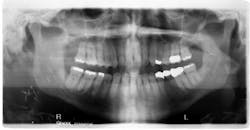

A panoramic radiograph showed the previously resected area was now fully displaced, and the musculature was causing rapid changes in the rotation of the two pieces away from each other (figure 2). The patient now had a fistula draining from the lower border of the mandible through the skin.